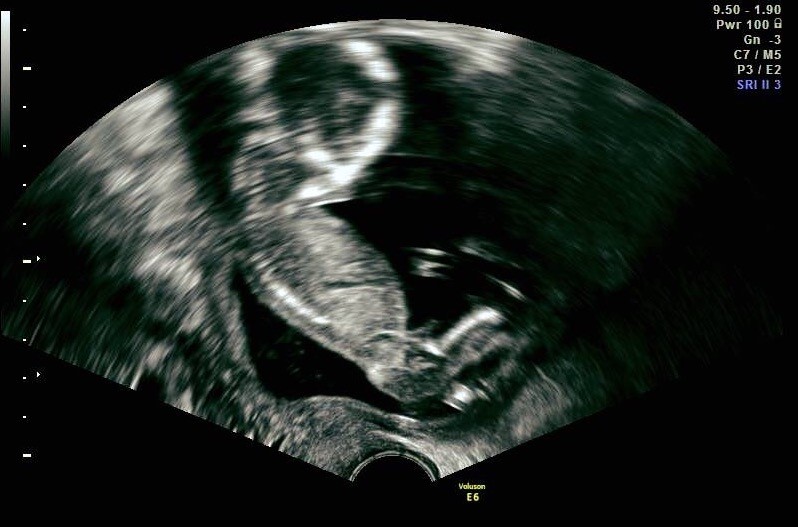

Her er scanningsbillederbe fra den gang  var i uge 16 da jeg fik kønsscanning.

Vedhæftede fotos (klik for at se i fuld størrelse)